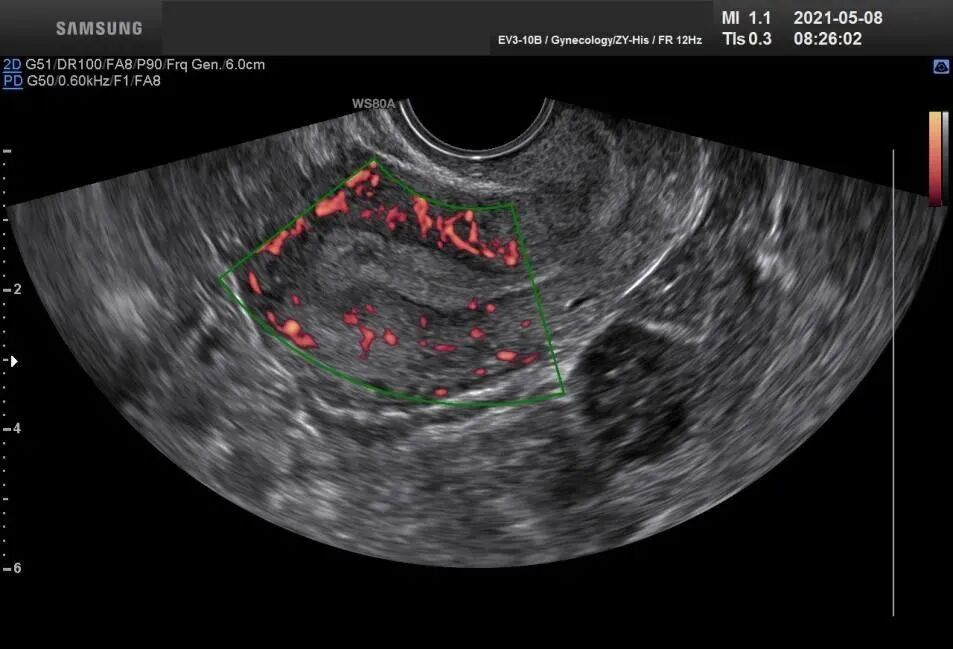

一般医生会先通过B超影像、照影检查及临床经验可以大致判断你的宫腔是不是有问题,如有异常,才需要做宫腔镜检查!

如:年龄、内分泌水平、超促排方案、胚胎质量、子宫内膜容受性等等,而最关键的因素在于胚胎的质量和子宫内膜的容受性。

在试管婴儿周期中,多数患者都可以得到优质胚胎,但获得妊娠的几率却不尽人意,其原因虽然未完全明了,但宫腔内存在的隐匿性微小病变对宫腔内环境造成的不良影响,却不容忽视。

而在进行宫腔镜检查治疗的过程中,子宫内膜受膨宫液的冲刷,宫腔均匀、机械性地扩张可能使内膜某些基因表达发生短时改变,促进内膜释放出有利于胚胎种植的生长因子和细胞因子,从而有利于胚胎着床,提高妊娠率。